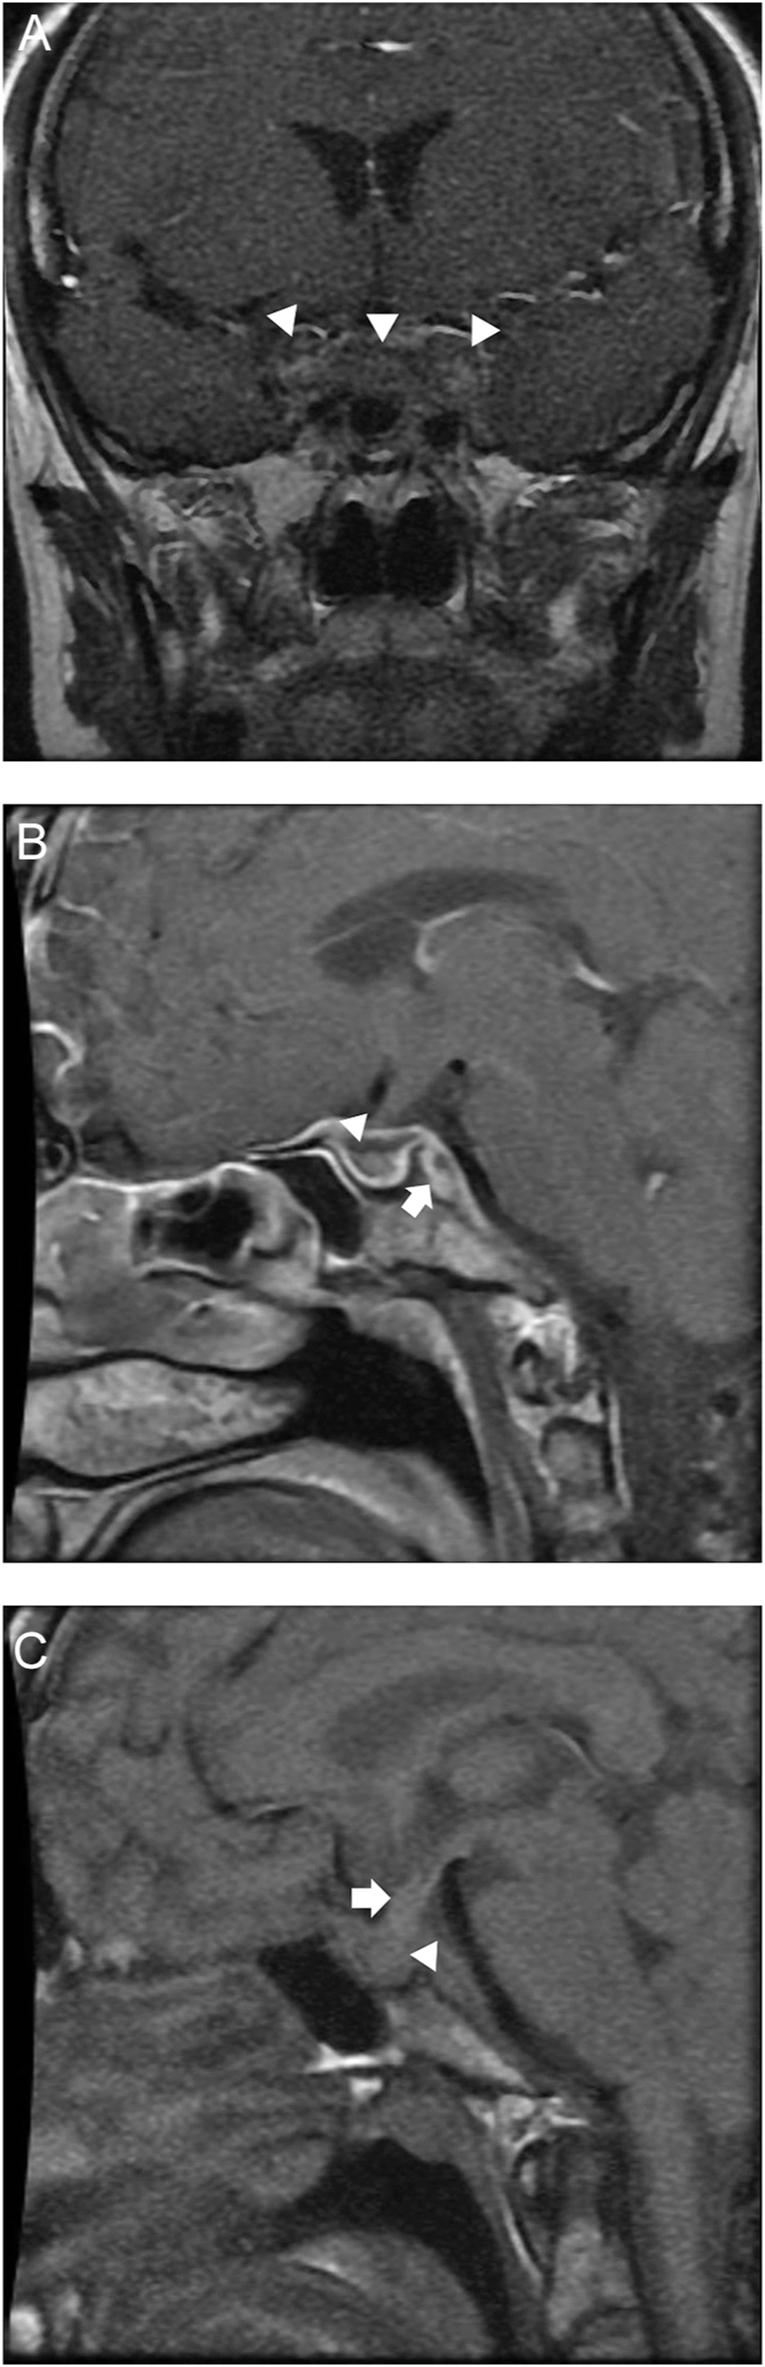

A 39-year-old woman presented with a 5-year history of severe intermittent headaches, rhinitis, hemoptysis, unintentional weight loss of 40 kg over a year, and unilateral vision loss. Then, she noticed polyuria, amenorrhea, muscle weakness, and cold intolerance. Diagnosis of granulomatosis with polyangiitis (GPA) was confirmed with elevated c-ANCA levels and PR3-positive antibodies. Physical examination revealed hypotension, absence of pubic and axillary hair, and classical signs of hypothyroidism. The patient reported multiple previous hospitalizations due to episodes of hypernatremia, hypotension, and hypoglycemia. The biochemical evaluation showed early signs of chronic kidney disease and central adrenal, thyroid, and gonadotropin deficiencies. Pituitary MRI revealed a heterogeneous pituitary gland with peripheral enhancement, central necrosis, and extension to adjacent structures, as well as the absence of posterior pituitary bright spot on T1-weighted imaging. A diagnosis of GPA with pituitary involvement was established. Remission therapy with corticosteroids and rituximab was started. After disease control, pituitary hormonal deficiencies persisted, requiring long-term hormone replacement therapy.

一名39岁女性,有5年严重间歇性头痛、鼻炎、咯血病史,一年来体重意外减轻40公斤,且有单侧视力丧失。随后,她出现多尿、闭经、肌肉无力和不耐寒。c-ANCA水平升高及PR3阳性抗体确诊为肉芽肿性多血管炎(GPA)。体格检查发现低血压、阴毛和腋毛缺失以及甲状腺功能减退的典型体征。患者报告此前因高钠血症、低血压和低血糖发作多次住院。生化评估显示有慢性肾病以及中枢性肾上腺、甲状腺和促性腺激素缺乏的早期迹象。垂体MRI显示垂体不均匀,周边强化,中央坏死并延伸至相邻结构,且在T1加权成像上垂体后叶亮点缺失。确诊为GPA累及垂体。开始使用皮质类固醇和利妥昔单抗进行缓解治疗。疾病得到控制后,垂体激素缺乏仍然存在,需要长期激素替代治疗。